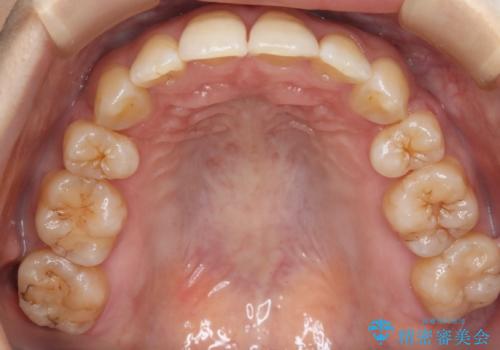

前歯を後ろに下げたい ワイヤー矯正(クリア装置)

- 前歯を後ろへ下げることを主訴に来院された患者様です。

10代の時に非抜歯でワイヤー矯正をしていました。

口元の突出感の改善や歯の移動量などを考慮し、抜歯を伴うワイヤー矯正での治療を選択しました。

抜歯を行うことで前歯を後ろへ下げるスペースを獲得し、口元の突出感や歯のガタつきを改善していきました。